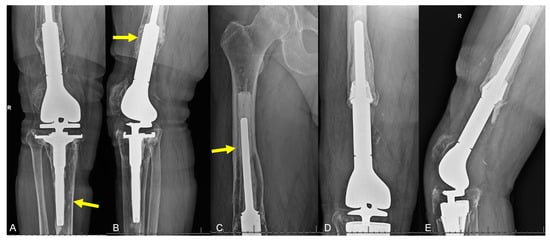

2.3.1. Structural Failure of Endoprostheses

- Type I: Fracture proximal to femoral knee component;

- Type II: Fracture originating at the proximal aspect of the femoral knee component and extending proximally;

- Type III: Any part of the fracture line is distal to the upper edge of the anterior flange of the femoral knee component.